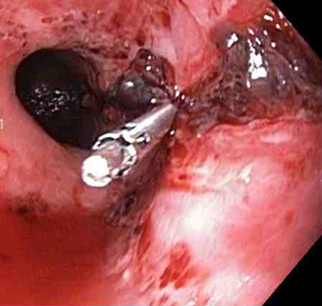

A through-the-scope clip deployed in the centre of the lesion (no previous adrenaline was infused in this case)

From the collection of Juan Carlos Munoz, MD, University of Florida